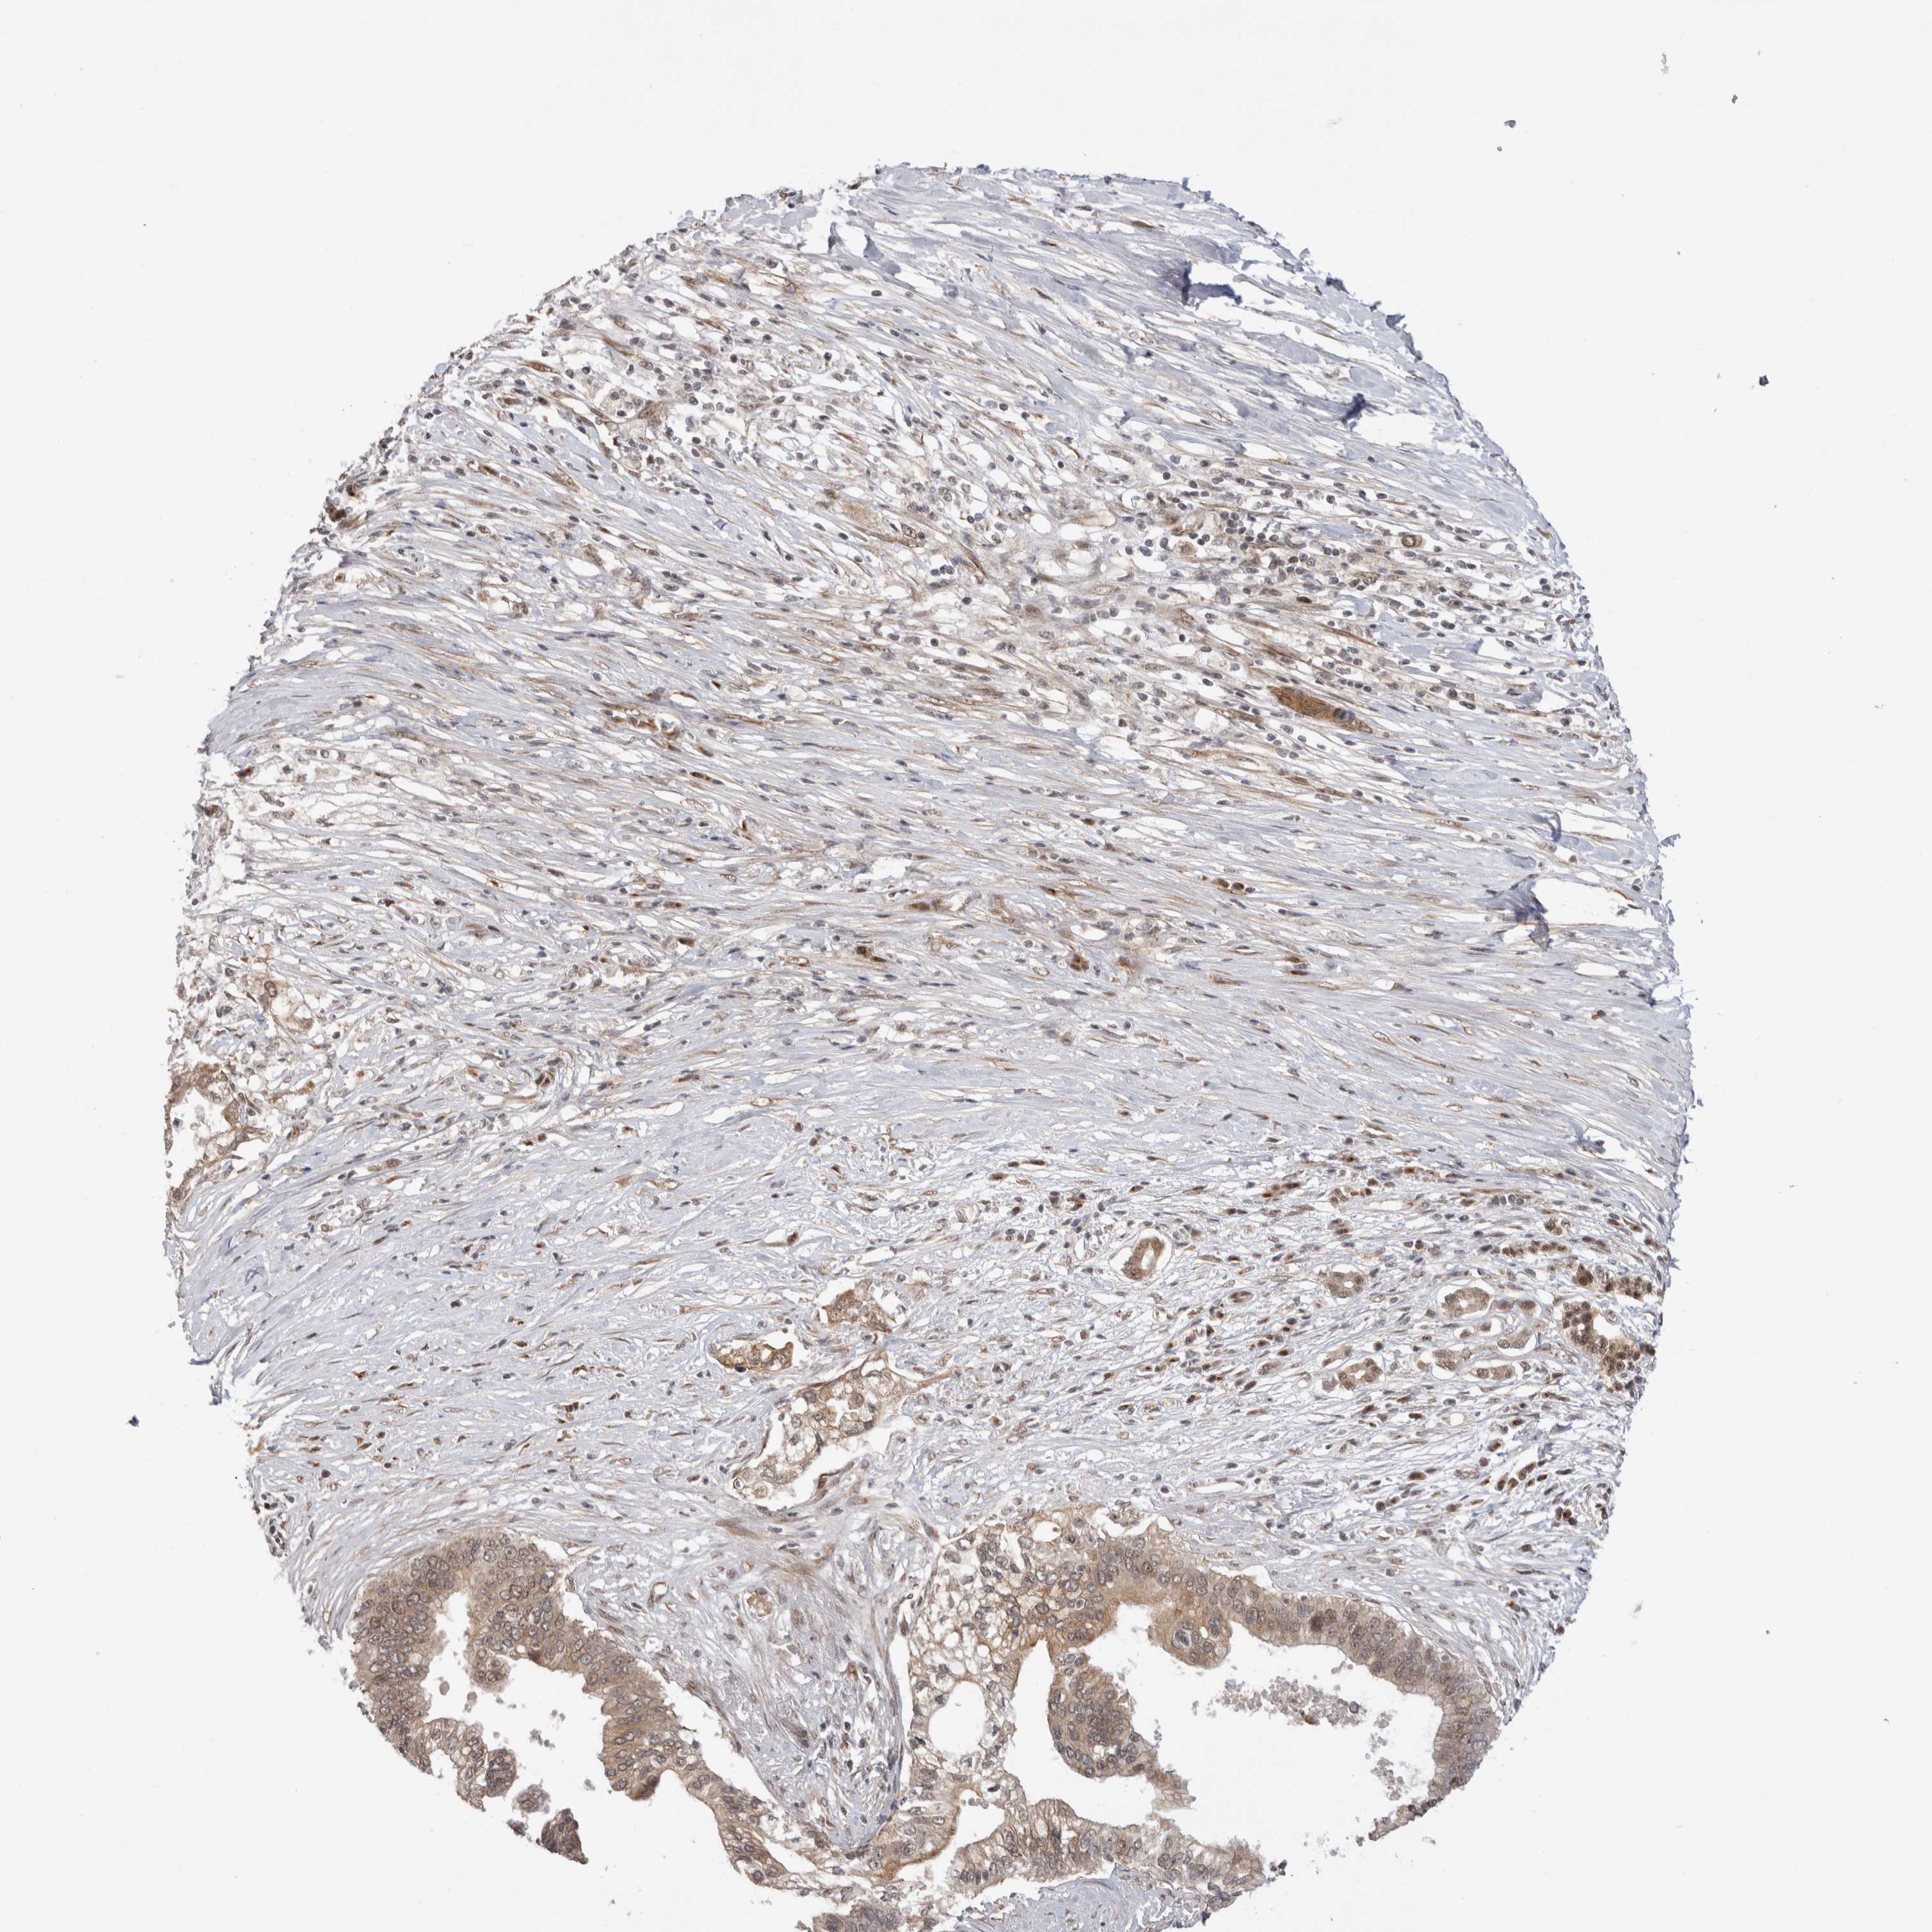

PANCREATIC CANCER - Protein expressioni

A mouse-over function shows sample information and annotation data. Click on an image to view it in a full screen mode. Samples can be filtered based on level of antibody staining by selecting one or several of the following categories: high, medium, low and not detected. The assay and annotation is described here.

Note that samples used for immunohistochemistry by the Human Protein Atlas do not correspond to samples in the TCGA dataset.

Antibody stainingi

Antibody staining in the annotated cell types in the current human tissue is reported as not detected, low, medium, or high, based on conventional immunohistochemistry profiling in selected tissues. This score is based on the combination of the staining intensity and fraction of stained cells.

Each image is clickable and will lead to virtual microscopy that enables deeper exploration of all samples and also displays staining intensity scores, fraction scores and subcellular localization as well as patient and tissue information for each sample.

Antibody HPA025020

Staining

High

Medium

Low

Not detected

Intensity

Strong

Moderate

Weak

Negative

Quantity

>75%

75%-25%

<25%

None

Location

Nuclear

Cytoplasmic/membranous

Cytoplasmic/membranous,nuclear

Adenocarcinoma, NOS